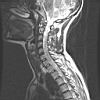

CWZ